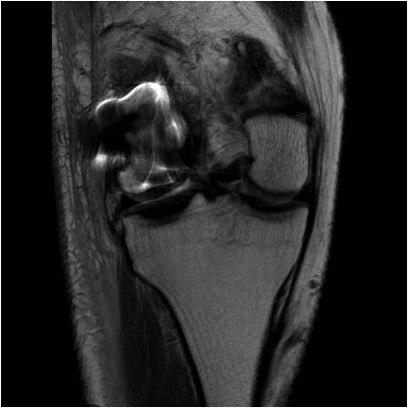

MRI

Excludes associated LCL / MCL injury

Hoffa Fracture MCL Avulsion MRI 1Hoffa Fracture MCL Avulsion MRI 2